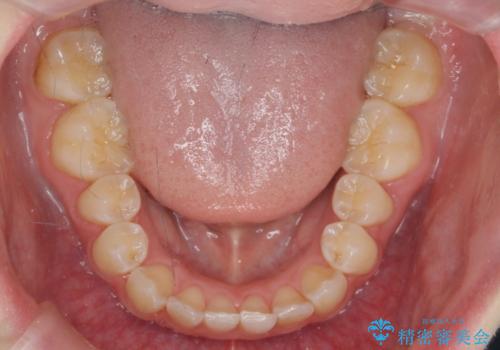

前歯のねじれを治したい マウスピース矯正治療

- 前歯のねじれを改善し、きれいな歯並びにしたい!と矯正治療を希望され来院されました。

マウスピース矯正システム、インビザラインのシミュレーションを用いて最終的な歯の位置をしっかりと確認したのち、きれいな歯並びとなるようマウスピース矯正治療を開始します。

ねじれとともに突き出たように見えていた前歯も見た目が大きく改善し、喜んでいただくことができました。